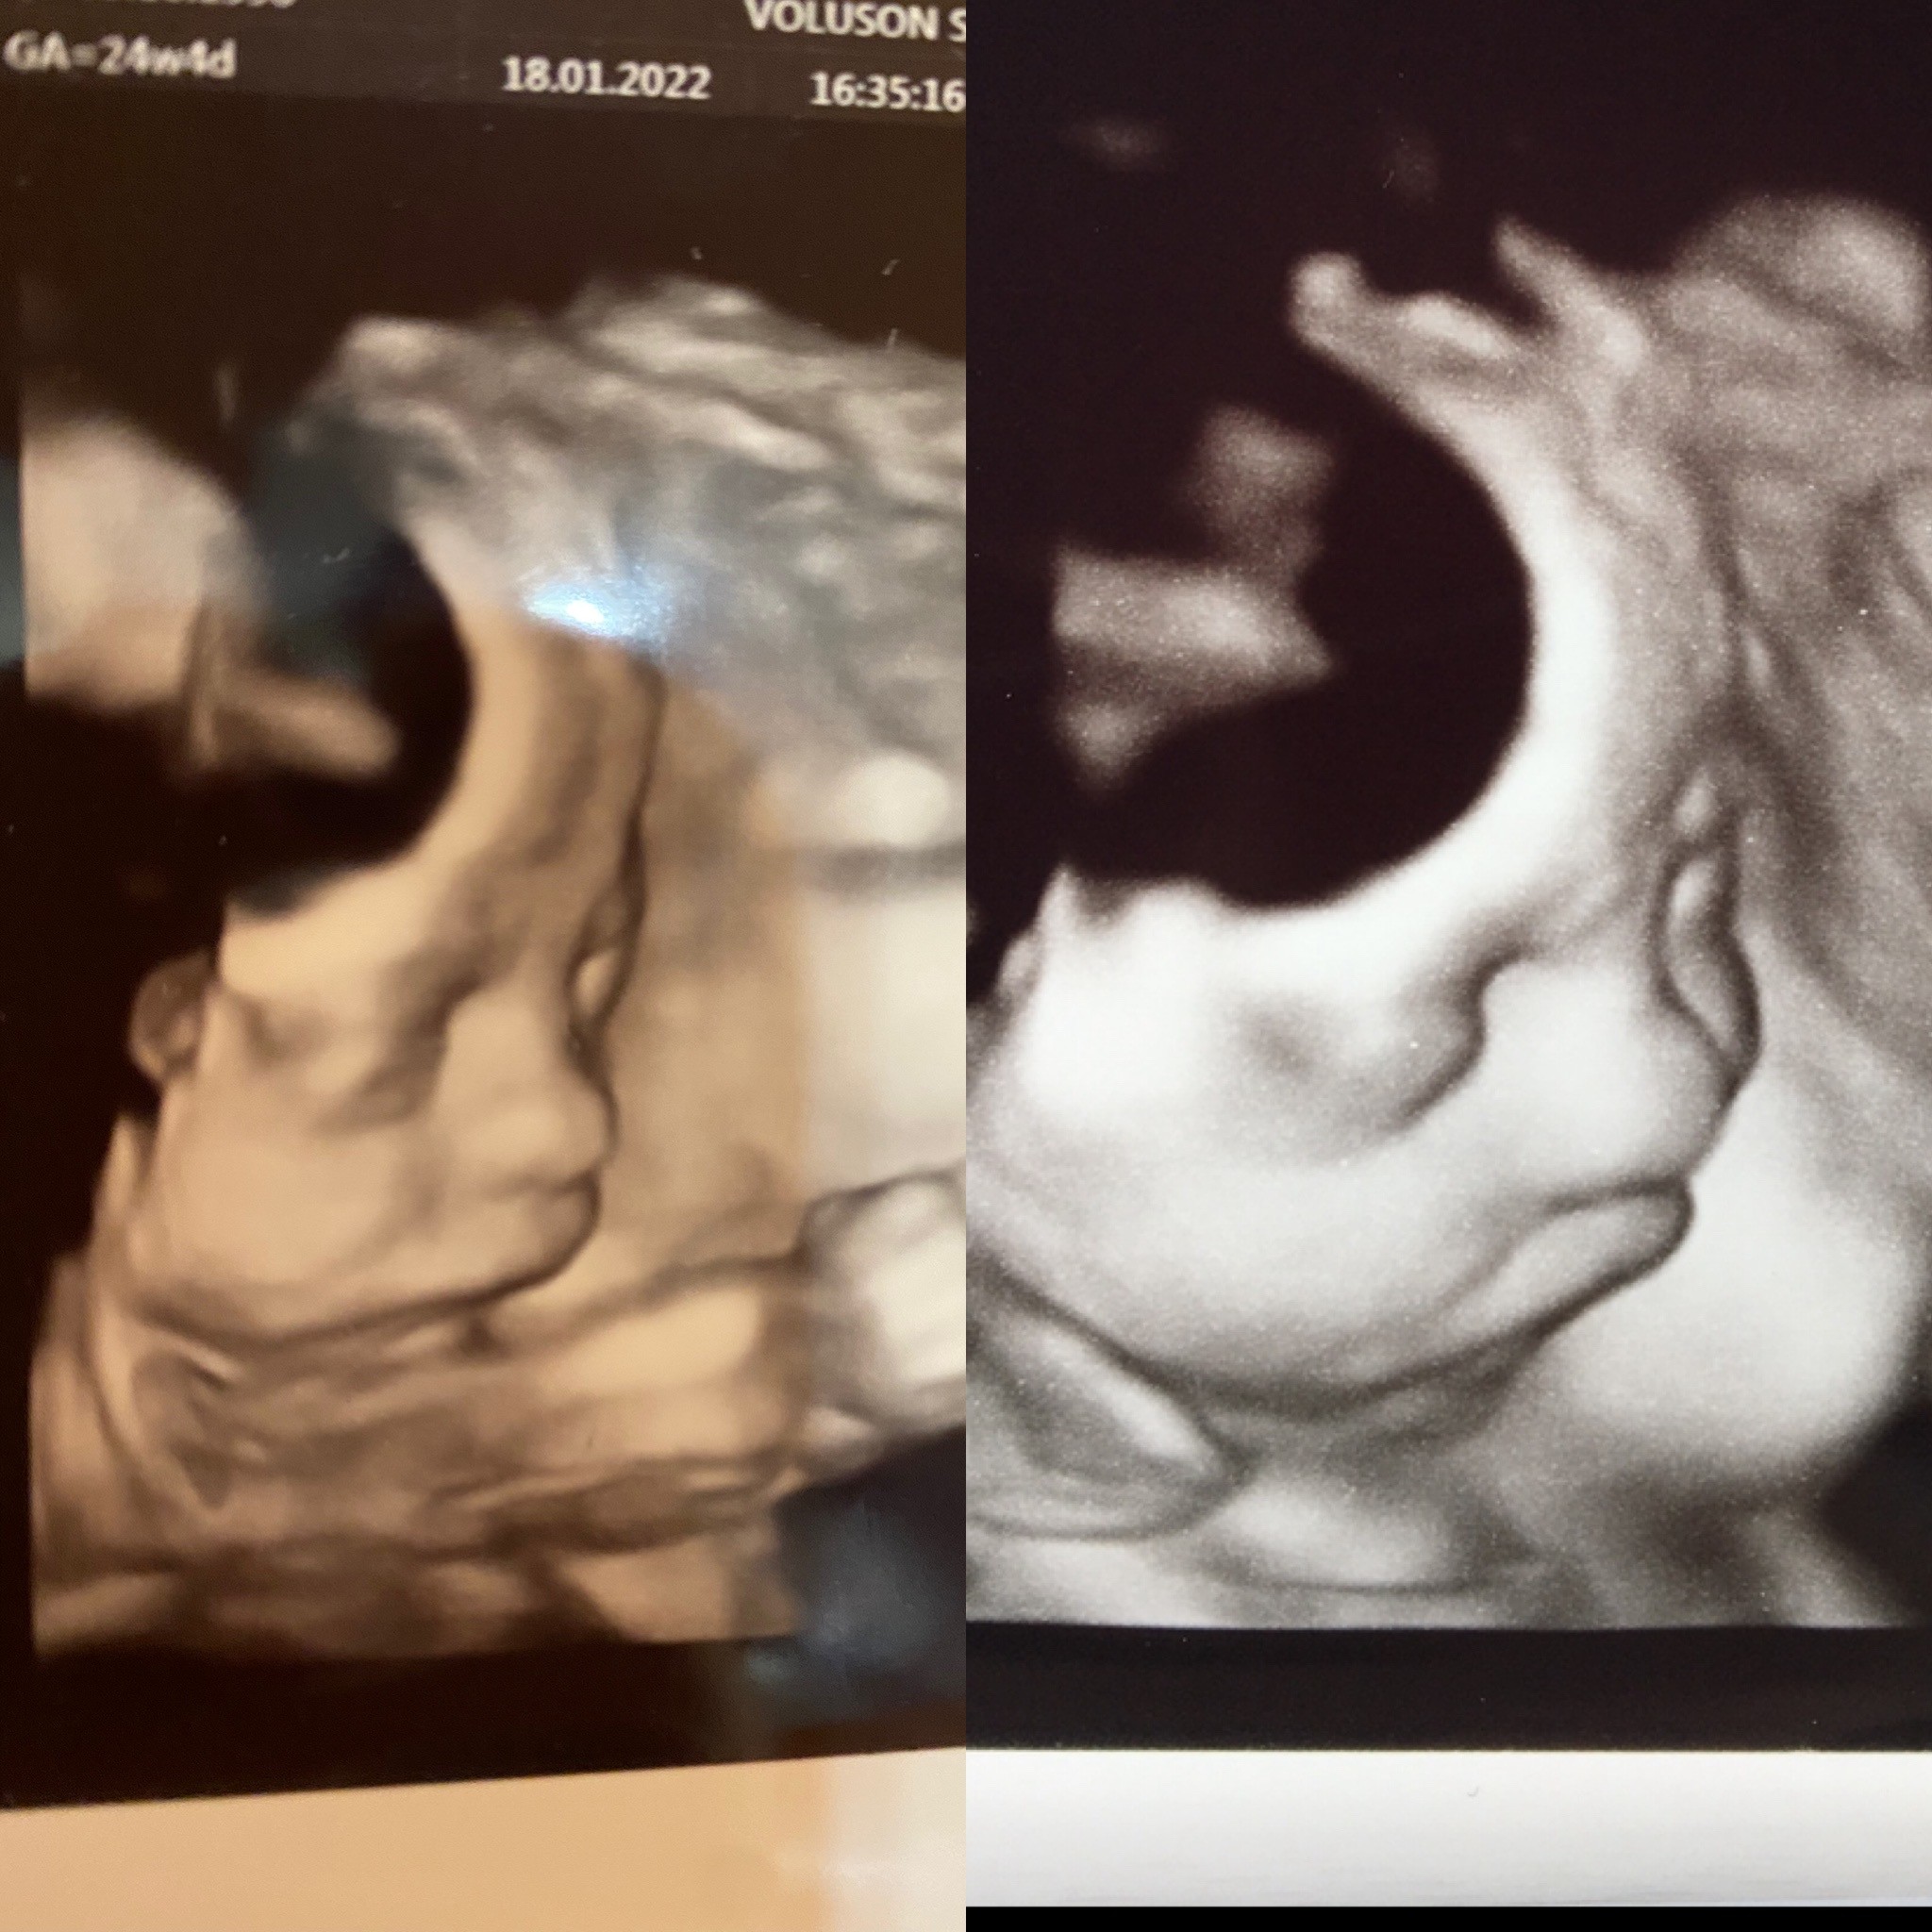

@Martitta88 u mnie wszystko ok po wizycie mała 24+4 z waga 720g😊. Oczywiście znowu cukrzyca ciążowa ale jeszcze bez insuliny, za tydzień mam kolejna wizytę u diabetologa to zobaczymy co wymyśli. Ciagle mam jakieś bakterie w moczu, już nawet lekarz się dziwi i tylko się zmienia albo pojedyncze, liczne albo dość liczne 🤷🏻‍♀️ Za tydzień mam powtórzyć i jak coś będzie to znowu na posiew (ostatnim razem był czysty)

Mała wydaje mi się bardzo podobna do Zosi.

(Po prawej Zosia 28+0, po lewej mała 24+4)😊